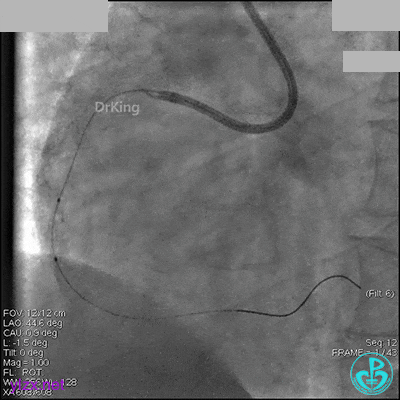

1周后再次上台,右冠脉3级血流,3段局限性严重狭窄,内膜模糊,应该是上次操作夹层遗留下的血肿。

先处理前降支开口严重狭窄并顺利植入前降支到左主干支架。